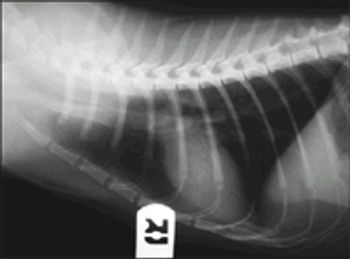

We place clear laminate sheets over our radiographs, so we can point out to clients what we are talking about without actually marking on the radiograph.